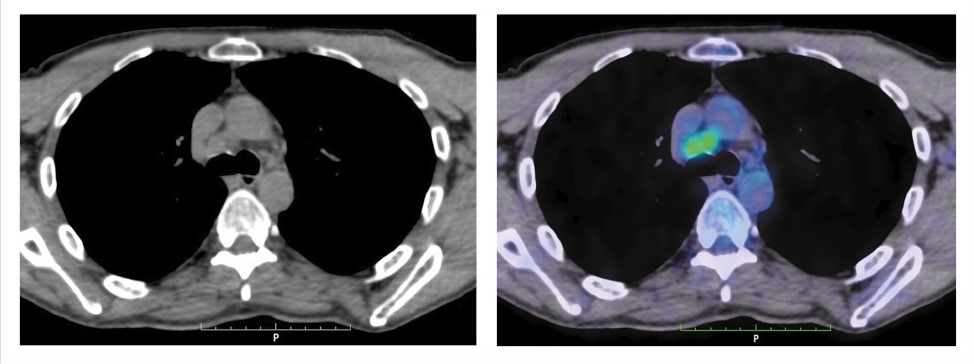

Кроме того, обнаружено увеличение всех групп внутригрудных л/у с гиперфиксацией РФП, SUVmax 8,7 (рис. 2).

Рис. 2. Пациент Т., 54 года. На аксиальных КТ- и ПЭТ/КТ-проекциях определяются увеличенные внутригрудные л/у всех групп, за исключением бронхопульмональных слева. Максимального размера – 19×27 мм – достигают бифуркационные л/у, SUVmax 8,7.